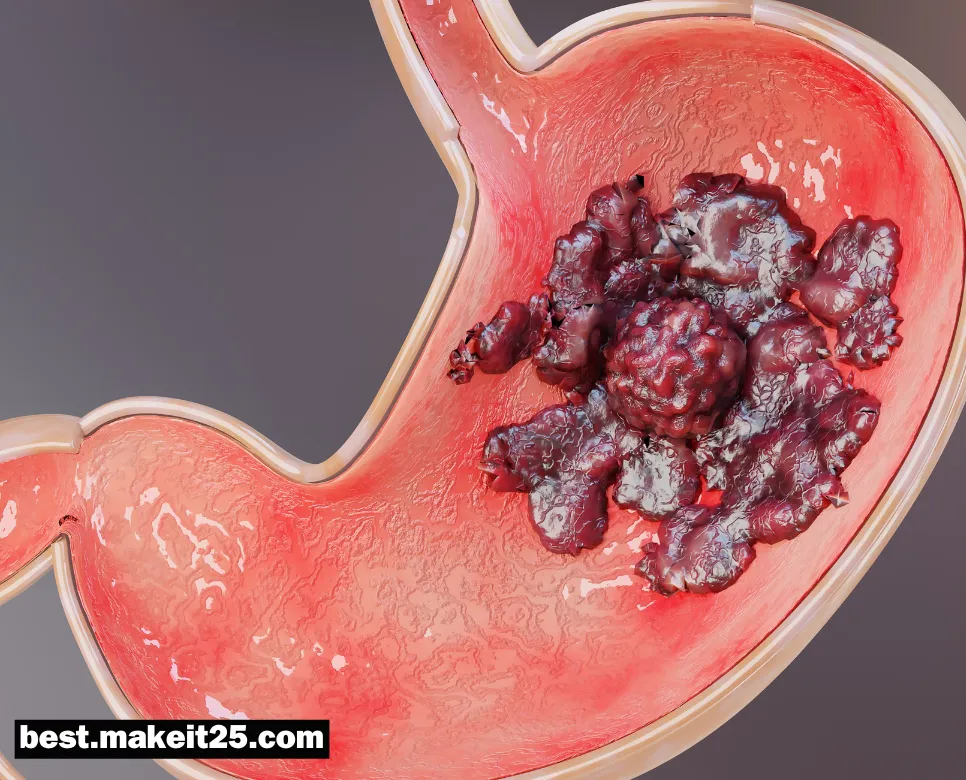

GIST(위장관 기질종양)

GIST는 Gastrointestinal Stromal Tumor의 약자로, 위장관 기질종양을 의미하는 의학용어입니다. GIST는 위장관의 벽을 구성하는 근육층에서 발생하는 종양으로, 위장관에서 발생하는 가장 흔한 연부조직 육종 중 하나입니다. 이 종양은 대부분 위나 소장에서 발생하지만, 식도, 대장, 직장 등 위장관의 어느 부위에서도 발생할 수 있습니다.

GIST의 원인과 위험 요인

- 대부분의 GIST는 Kit 또는 PDGFRA 유전자의 돌연변이로 인해 발생합니다. 이러한 돌연변이는 종양 세포의 비정상적인 증식을 유발합니다.

- GIST의 발병률은 연령이 증가함에 따라 높아지며, 대부분 50대 이후에 진단됩니다.

- 남성과 여성에게서 비슷한 빈도로 발생합니다.

GIST의 증상

GIST의 증상은 종양의 크기와 위치에 따라 다양하게 나타날 수 있습니다. 작은 종양은 증상이 없을 수도 있지만, 종양이 커지면 다음과 같은 증상이 나타날 수 있습니다:

- 복부 불편감 또는 통증

- 위장관 출혈로 인한 혈변 또는 빈혈

- 복부 종괴가 만져질 수 있음

- 식욕 감소, 체중 감소, 피로감 등의 전신 증상

그러나 이러한 증상은 비특이적이므로, GIST의 진단을 위해서는 영상 검사와 조직 검사가 필요합니다.